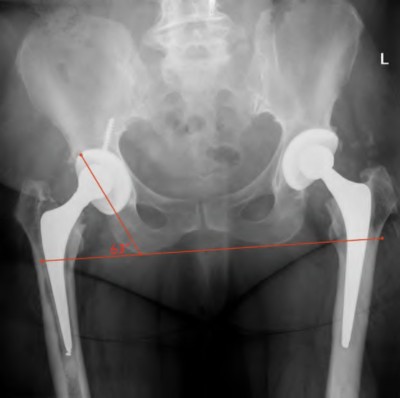

A surgeon is planning to revise a left hip resurfacing component to a total hip arthroplasty. He wishes to decrease the joint reaction force of the left hip by increasing the femoral offset. Which of the following labeled measurements found in Figure A best describes femoral offset?

In total hip arthroplasty, the femoral component offset is measured as distance between the center of the femoral head and a line drawn down the center of the femoral shaft(Line 4 shown in Figure A). Increased femoral offset is also shown in Illustration A.

The review article by Bourne et al states that offset is relevant to soft tissue balancing around the hip and the forces generated at the hip joint.

Lateralization of the femoral shaft restores offset, reduces femoropelvic impingement, and increases abductor muscle tension leading to a decreased joint reaction force. However, increasing femoral offset may have the unwanted effect of increasing rotational torque on the stem leading to aseptic loosening and increasing trochanteric bursitis.